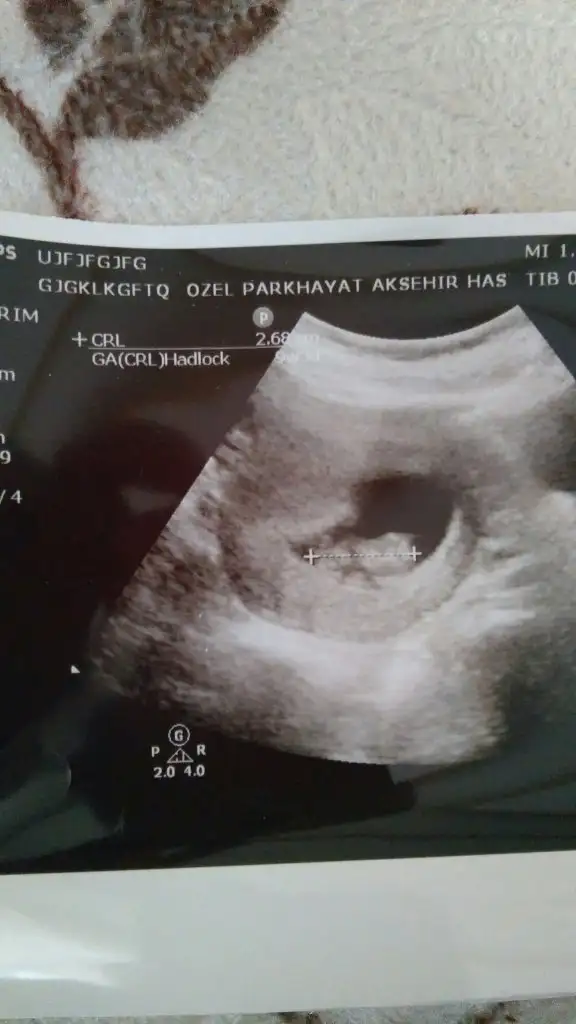

Boyle bi goruntusu var teyzeleri icimden kiz geciyor ama doktor bu goruntu kizda da boyle erkekte de boyle gorunur dedi 10 gun sonra bakalim tekrar cinsiyet icin dedi